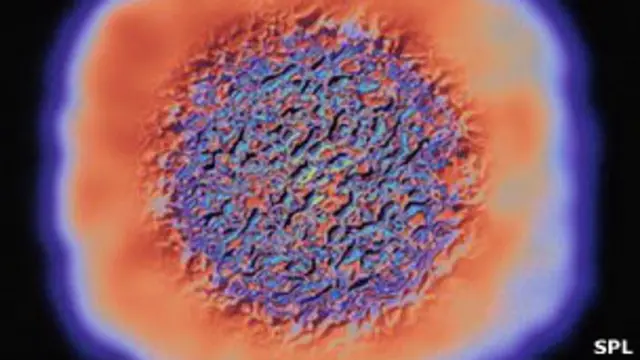

Estos trastornos son causados por defectos en la mitocondria, el "motor" de las células, y pueden causar síntomas como atrofia muscular, ceguera, enfermedades intestinales y cardíacas afectando severamente a los pacientes y reduciendo sus expectativas de vida.

La mitocondria es la encargada de proveer energía a cada célula en el organismo.

Ésta se transfiere en el óvulo de la madre hacia el bebé. El padre no transfiere mitocondria en el esperma.